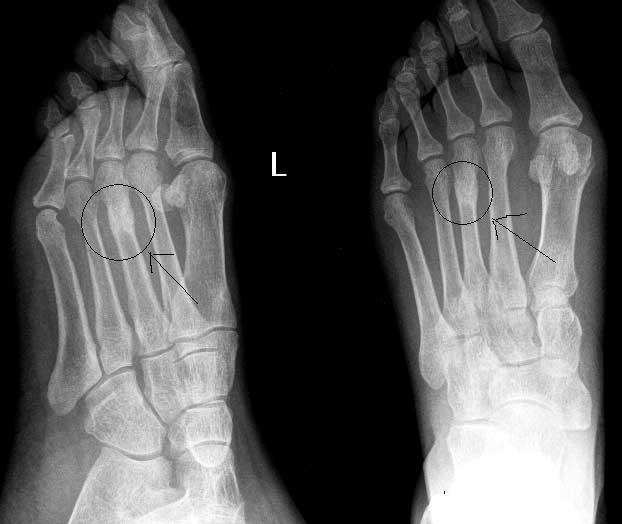

以下是引用常山真人在2004-7-20 9:50:49的发言:[br]第3遮骨疲劳性骨折[br]左足第1趾-似---囊性病变(片不太清晰) 1-正常 2-如是囊性病变多为内生性软骨瘤。[br][br][本贴已被 常山真人 于 2004-7-20 9:53:09 修改过]

以下是引用rjbjl在2004-7-20 21:39:14的发言:[br]应该是第三蹠骨疲劳型骨折[br]zhi骨

以下是引用www123456在2004-7-20 23:17:45的发言:[br]典型的第三跖骨 疲劳骨折。[br]对于第一趾骨的病变怀疑是没有根据的,斜位所见影像是由于第一趾的跖趾关节软组织和骨皮质凑成的。在正位片可见第一趾的骨质是完好的。